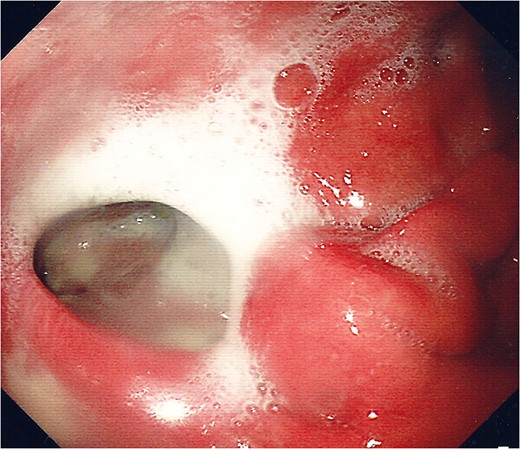

For management of this oesophageal perforation and definitive management of her gastric perforation, the patient was referred to the authors’ unit, a tertiary referral centre for upper GI surgery. In the first instance, a water-soluble contrast swallow was performed to assess the status of the oesophageal perforation. This demonstrated no leak of contrast (Fig. 3) and therefore a diagnostic endoscopy under general anaesthesia was performed in order to assess the cervical oesophagus and also the known gastric perforation. This endoscopy demonstrated a healed oesophageal perforation but persistent gastric perforation with established cavity (Fig. 4) containing an existing transabdominal Robinson drain. The cavity was felt to be of a size likely to heal without the need for further negative pressure vacuum therapy, so a T-tube was placed across it. The established track of the existing abdominal drain was used to guide placement of the T-tube. A nasojejunal feeding tube was placed under vision.

Endoscopic photograph showing perforation of the posterior gastric wall with established cavity.